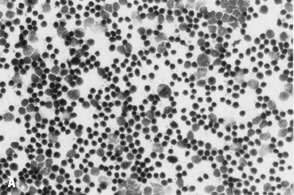

Physiologic (functional) cysts of the ovaries usually appear benign (i.e., thin-walled, unilocular, and not more than 5 cm in diameter) on ultrasound examination; however, they may mimic malignant tumors.77 Aspirates generally contain follicular cells, typically granulosa cells, arranged both singly and as tightly cohesive fragments (Fig. 10). These cells house ovoid nuclei with granular chromatin and occasional nuclear grooves, and they have a small rim of distinct cytoplasm; mitoses may be present.100 The background of the smear typically shows clear, proteinaceous material but may be bloody.77 Cyst fluid from functional cysts of folliculogenesis typically have a high estrogen content. Mulvany and colleagues101 reported a sensitivity of 84% for the detection of follicular cysts by estrogen assay. As a follicular cyst undergoes luteinization, cytomorphologically altered granulosa cells appear with prominent nucleoli and more ample granular cytoplasm.100 Cytoplasmic hyaline droplets may be seen in the corpus luteum of pregnancy.82 On occasion, fluid aspirated from functional cysts may be highly cellular, with cells featuring high nuclear-to-cytoplasmic ratios and hyperchromasia; papillary clusters and even small glandular structures may be noted.102,103 Clinical and radiologic impressions, as well as the presence of well-preserved granulosa cells in the smears, are helpful for reaching the correct diagnosis.103 The granulosa cells lining follicular cysts are immunohistochemically negative for cytokeratins, whereas those epithelial neoplasms considered in the differential diagnosis would be immunoreactive with antibodies directed against cytokeratins.102

Fig. 10. A. Fluid aspirated from a unilocular ovarian cyst in a young woman shows small, cohesive aggregates of benign lining cells from the inner granulosa cell layer of a functional (follicle) cyst; the cells are intermediate in size with round, vesicular nuclei and scant cytoplasm (stain, Papanicolaou; courtesy of Bradford Tan, M.D.). B. Corresponding histologic section of a follicular cyst shows orderly layering of granulosa/theca cells in the cyst wall with bland nuclear features, similar to that seen in the aspirated fluid (stain, hematoxylin-eosin).